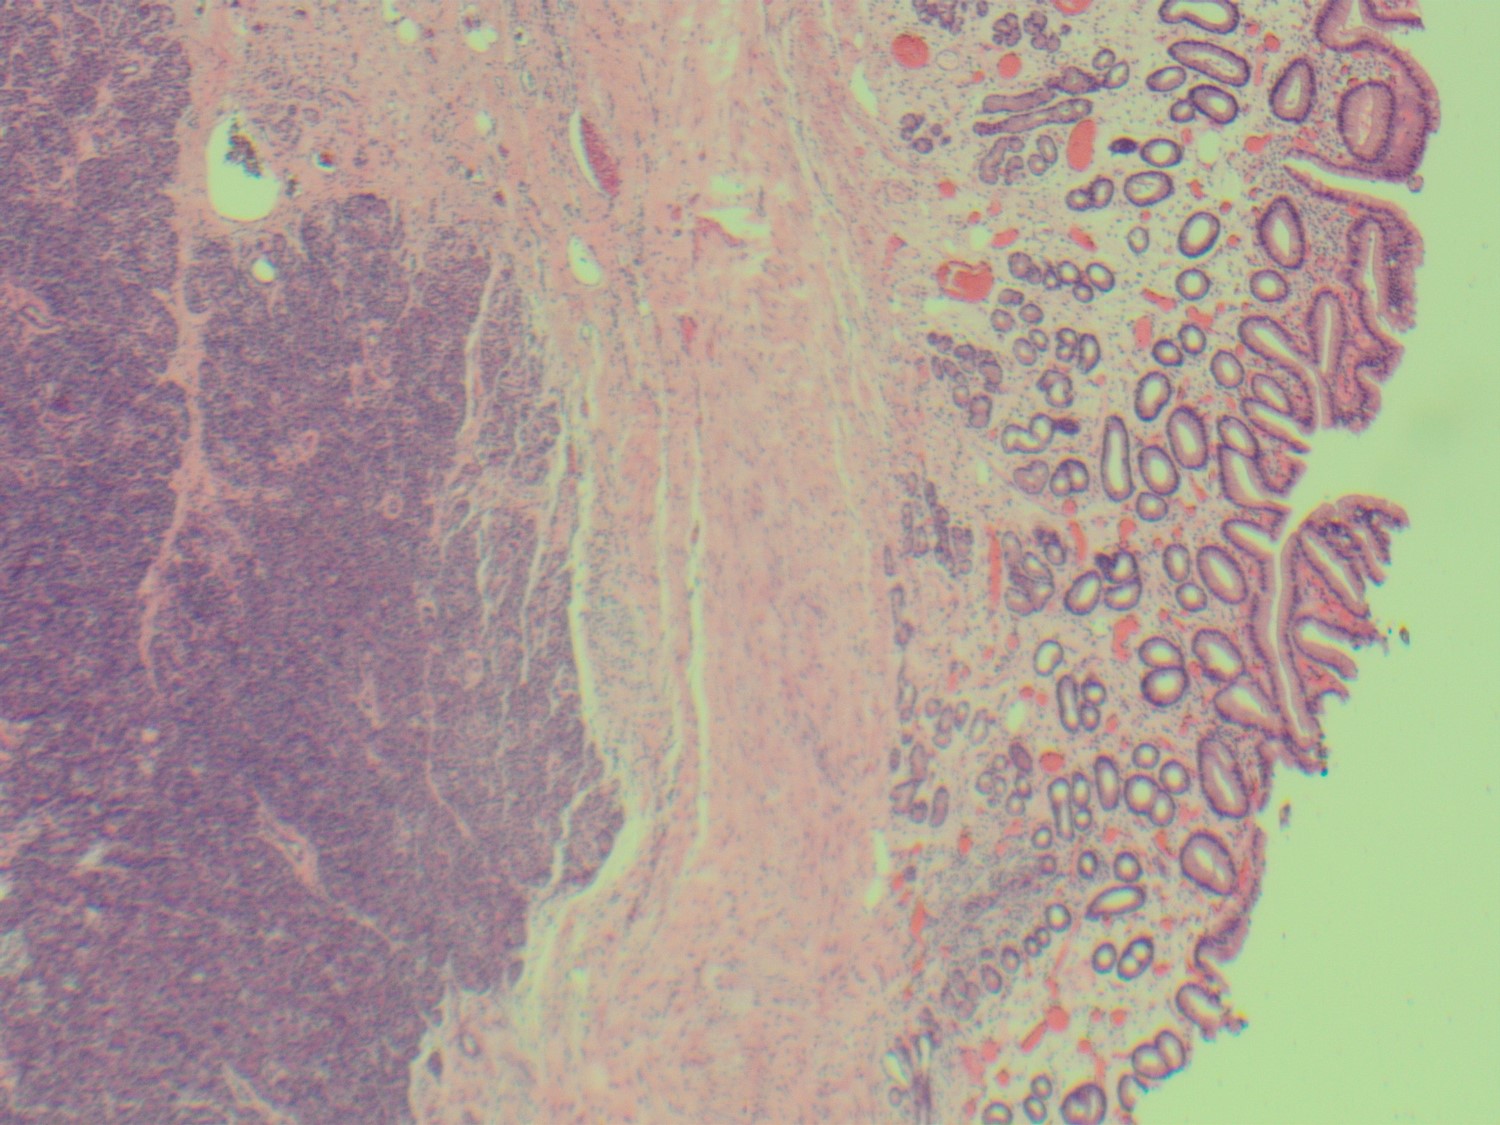

The lesion was resected, showing a submucosal rest of histologically normal pancreatic parenchyma (Fig 5-7).